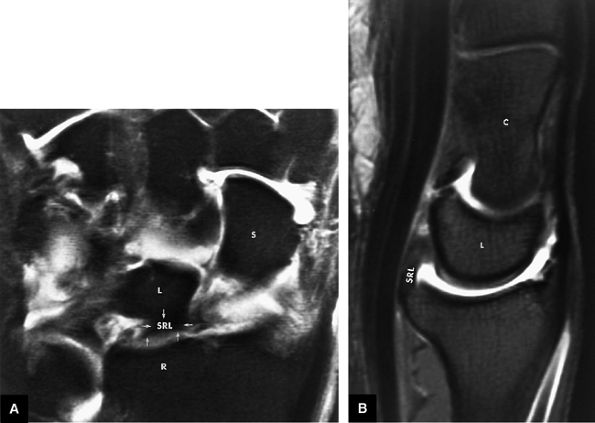

FIGURE 10.63 ● The long radiolunate or radiolunotriquetral (RLT) ligament. (A) The RLT ligament is divided into a radiolunate ligament and lunotriquetral component. The RLT ligament functions as a volar sling for the lunate. L, lunate; R, radius. Volar FS coronal T1-weighted arthrogram. FS axial T1-weighted arthrograms obtained at the level of the proximal (B) and distal (C) aspects of the radial styloid show the volar course of the RLT ligament (large arrows) from the radial styloid (R) inserting into the lunate (L) and blending with the volar portion of the lunotriquetral interosseus ligament. The lunate attachment of the scapholunate interosseous ligament volar fibers is deep to the lunate attachment of the RLT ligament (B). S, scaphoid; T, triquetrum; SL, scapholunate ligament.

FIGURE 10.62 ● Anatomy of the radioscaphocapitate (RSC), radiolunotriquetral (RLT), and radioscapholunate (rsl) ligaments at the level of the distal volar radius (R). T, triquetrum; S, scaphoid. FS T1-weighted arthrogram after radiocarpal injection.